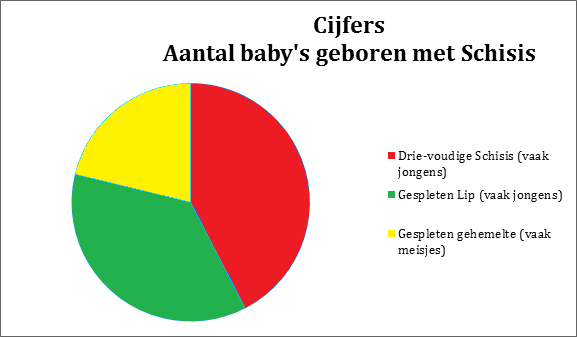

Cijfers:

- Eén op de zeshonderd kinderen in Nederland worden geboren met een Schisis.

Hiervan heeft ongeveer 43% een drievoudige Schisis en deze komt het meeste voor bij jongens.

- Ongeveer 36% van de kinderen worden met alleen een gespleten lip geboren en ook dit komt het meeste bij jongens voor.

- De overige 21% van de kinderen wordt met een gespleten gehemelte geboren en dit zijn vaak meisjes.